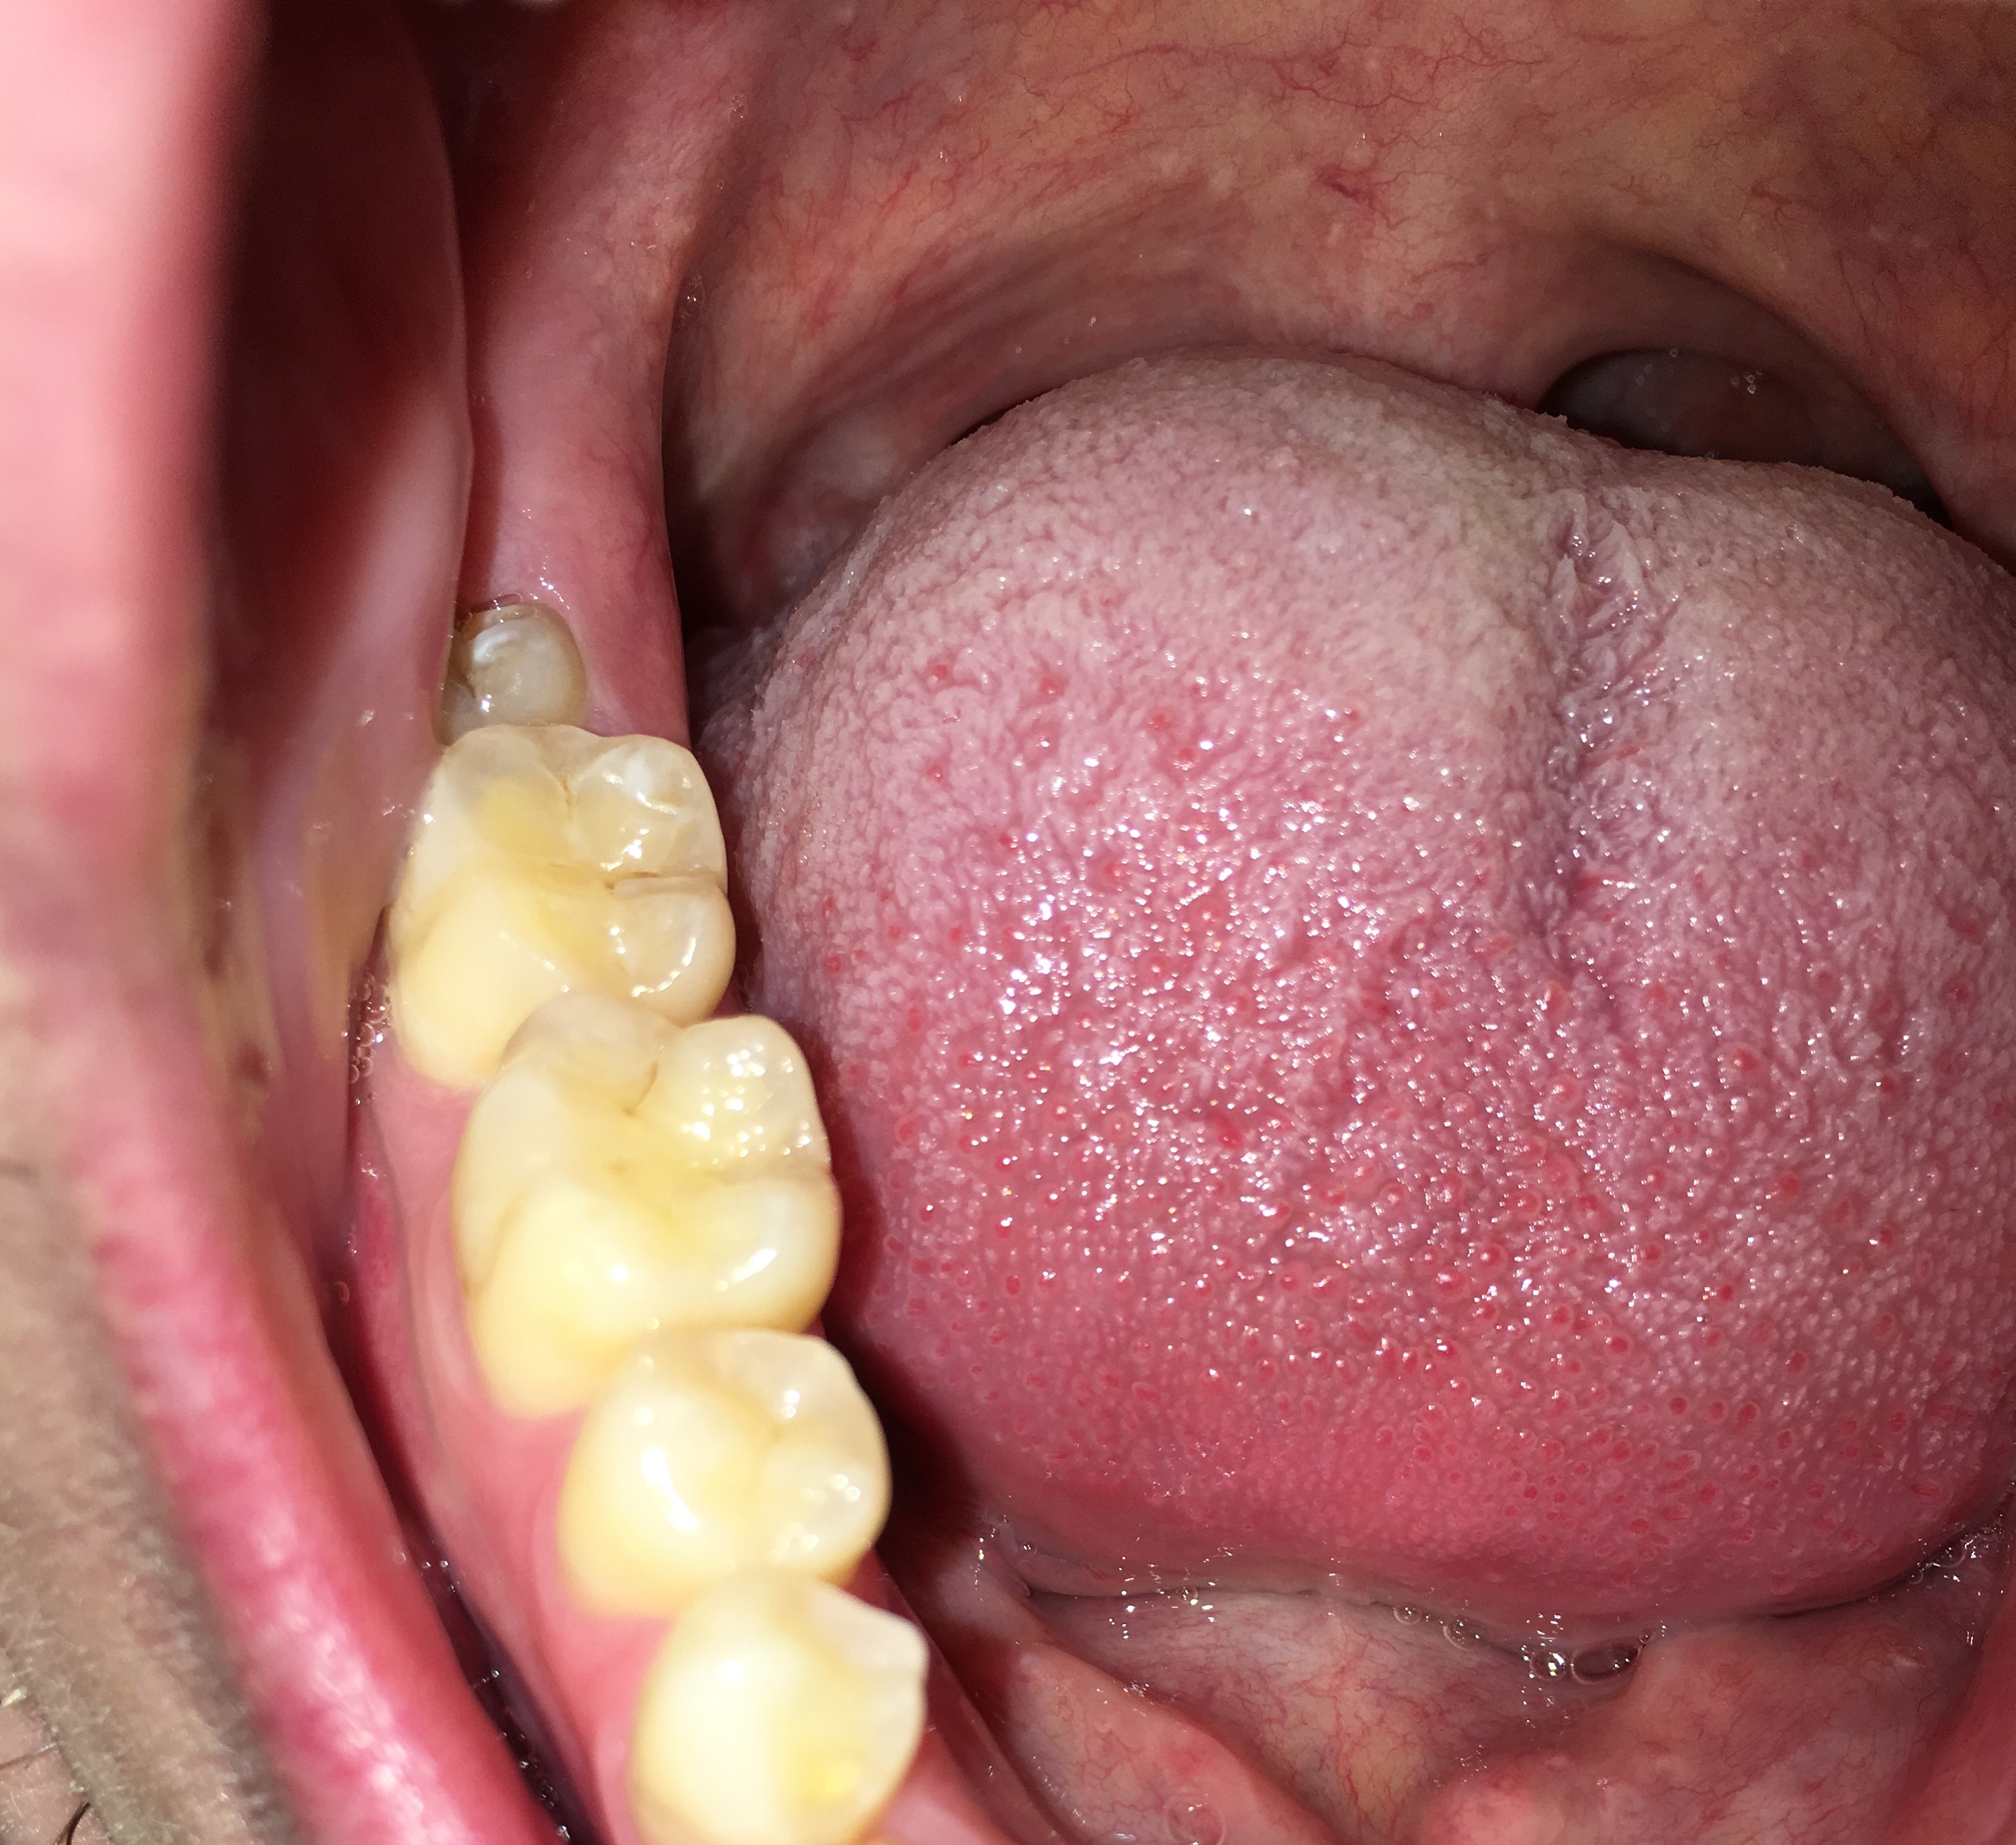

Hierbij 3 foto's van mijn onderkaak. De eerste foto is van mijn linker onderkaak van 2017, de tweede foto is van mijn rechter onderkaak van 2017 en de laatste foto is van 2015 van mijn gehele onderkaak. De foto van 2015 is met een andere telefoon genomen, hierdoor is de kleur en belichting wat anders, echter zie ik bij alle drie de foto's en de foto van 2025 de zelfde hoeveelheid doorzichtigheid.